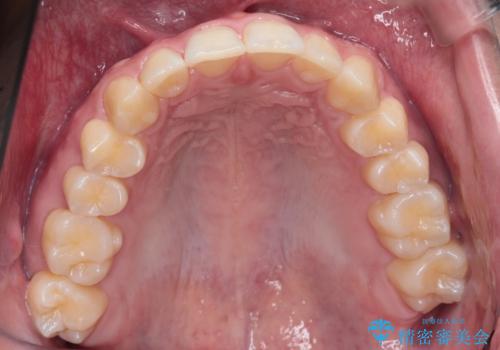

【インビザライン】短期間で出っ歯を治したい

- 出っ歯と口元の突出感が気になるということで来院されました。抜歯矯正も考えられますが、今回は早く終わらせたいという要望があり非抜歯での治療にしました。また遠方から来院されているため、来院回数のおさえられるインビザラインを選択しました。

非抜歯での治療のため、今回はスペース確保のために遠心移動とおもにIPRの処置を取り入れました。